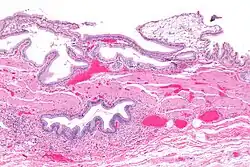

Mikrofoto von Cholezystitis. Cholezystektomie. HE-Färbung.

Die Cholezystitis, Cholecystitis oder Gallenblasenentzündung bezeichnet eine Entzündung der Gallenblase, die in den meisten Fällen (90–95 %) durch Gallensteine verursacht wird.